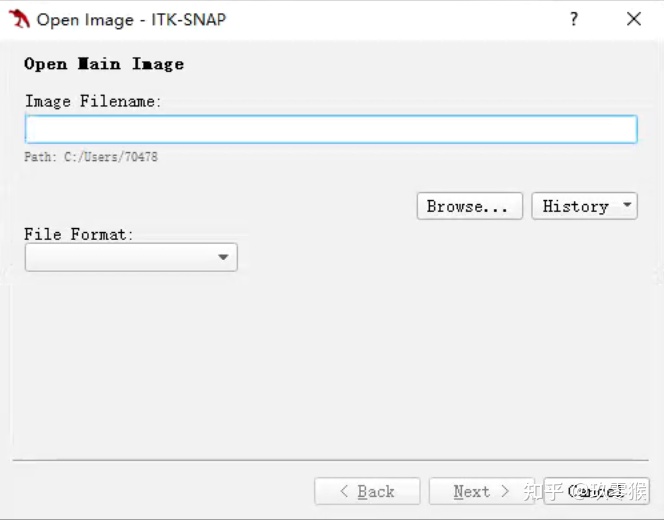

1、导入医学图像( nii.gz文件)

File->Open Main Image

点击 Browse... (切记不能有中文路径) -> Next

1、导入医学图像( nii.gz文件)

File->Open Main Image

点击 Browse... (切记不能有中文路径) -> Next